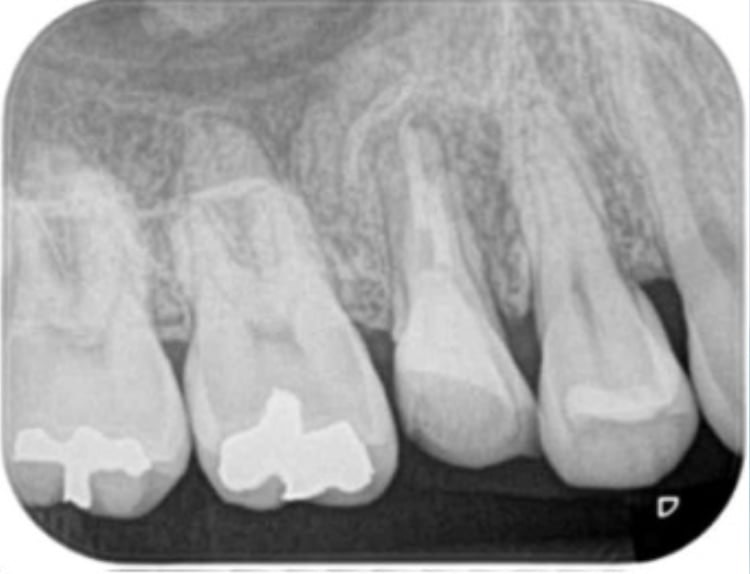

根管治療(初回の神経の治療)

歯の内部が感染しないようにする。もしくは感染してしまったのを治す治療です。

術前

術後

初回の根管治療の成功率は比較的高く細菌感染レベルが低い場合は適切に治療すればGP(一般歯科医)でも成功する可能性は高いと思われます。ただし、術者の歯内療法におけるトレーニングの習熟度により成功率にばらつきが出ます。

日本全国で行われている一般的な根管治療の成功率は50%以下と推測されます。(日歯内療誌 32(1): 1~10, 2011より私的解釈)